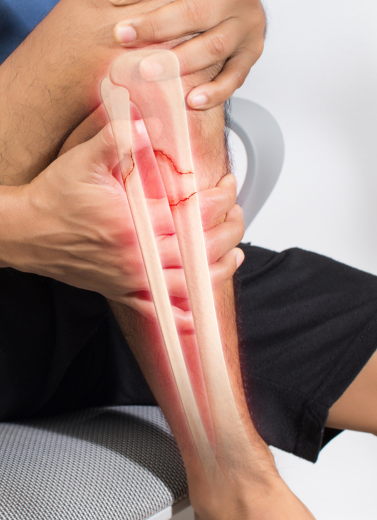

Complex & Comminuted Fractures

Non-Union or Delayed Healing Fractures

Accident or Road Injury-related Trauma